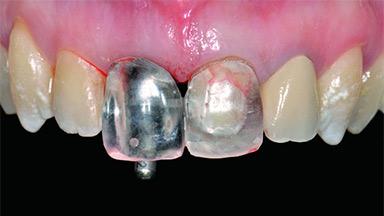

A 30-year-old patient presented at our clinic with a chief complaint of pain in her endodontically treated right maxillary central incisor (tooth 11) with a post-and-core and a fixed single crown. She had a very high lip line, a medium to thin soft-tissue phenotype, and a medium scalloped gingival contour. She also had high esthetic expectations because of her young age and beautiful smile. However, her expectations were realistic and she understood the risks of the treatment. At the initial clinical examination there was a slight mobility of tooth 11; no fistula was observed. The patient also had a single crown on the adjacent tooth 21. Both restorations were old and esthetically deficient. A digital periapical radiograph showed a very small periapical radiolucency, a thick intraradicular post, and no separation between root fragments.

Prosthesis Type FDP

Provisional Implant-Supported Prosthesis Prosthodontic margin > 3 mm apical to mucosal margin Prosthodontic margin > 3 mm apical to mucosal margin

Interim Prosthesis during Healing Fixed Fixed